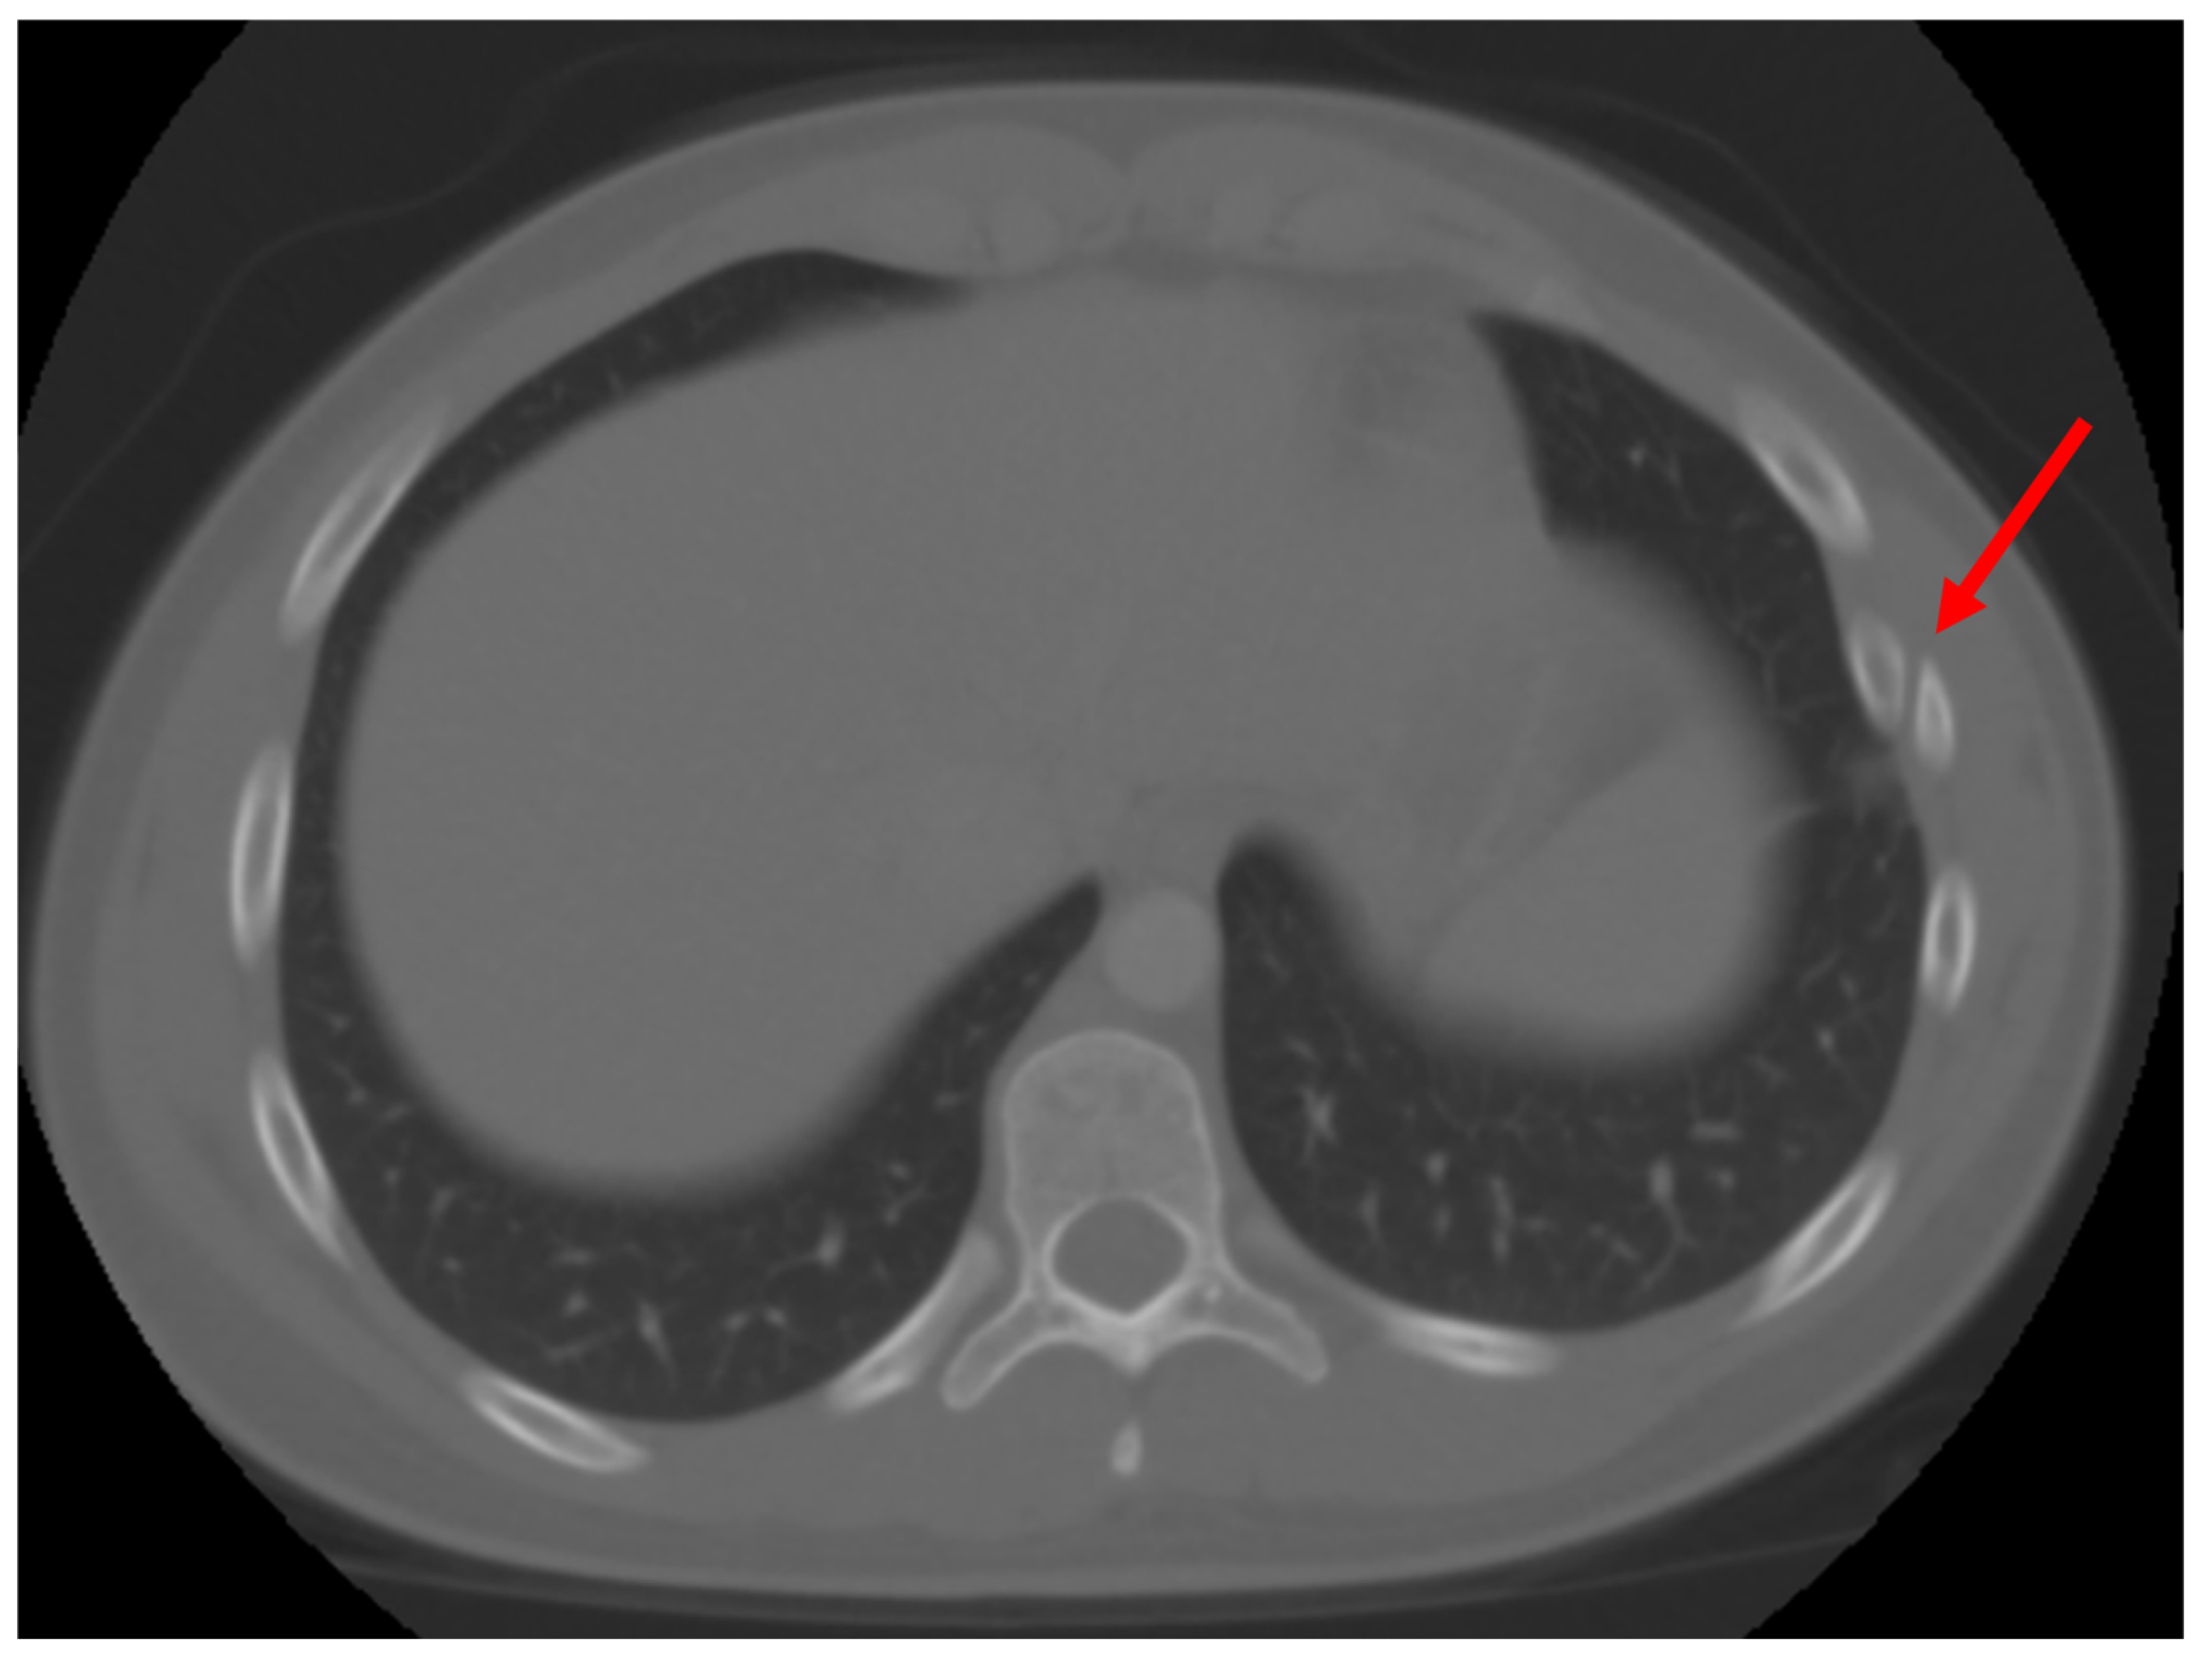

Figure 4.

Non-union fracture of the 7th rib. Red arrow points to the location of injury.